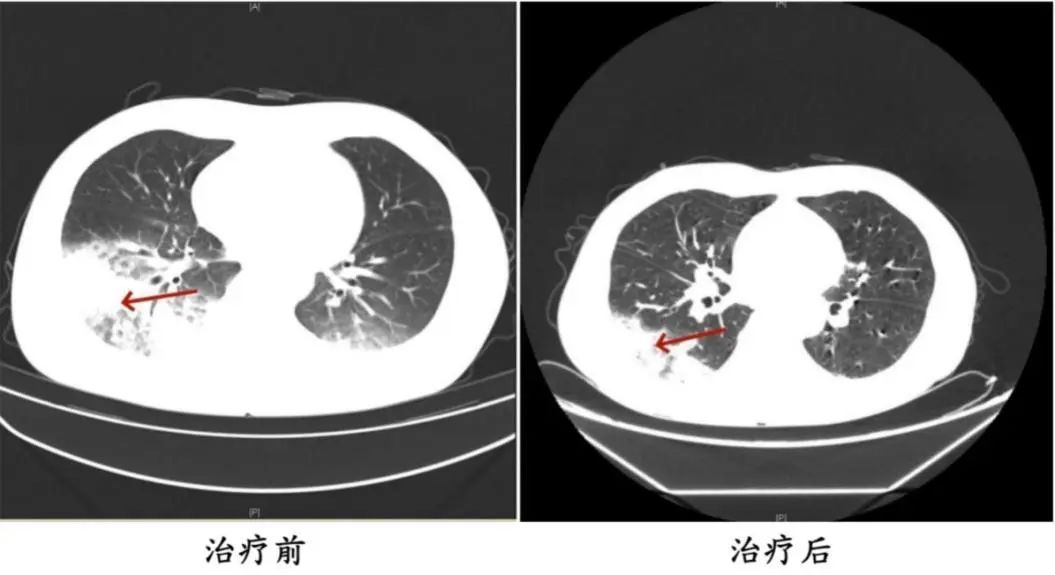

周先生治疗前后的肺部CT影像

2024年,55岁的长沙市民周先生(化姓)有2型糖尿病、2型糖尿病性肾病、慢性肾功能不全等多个既往史,因持续发热、寒战、咳嗽前往医院就诊,检查发现肺部存在严重感染,应用抗生素抗感染治疗后效果不佳,患者依然持续发热,还出现了神志淡漠的异常表现。医生询问发现,周先生此前驾车出差,因为天气热,他启动了久未清洗的车载空调,每天在车上的时间超过十个小时,回来后就出现了如上症状。经过检查,最终确诊为军团菌肺炎。